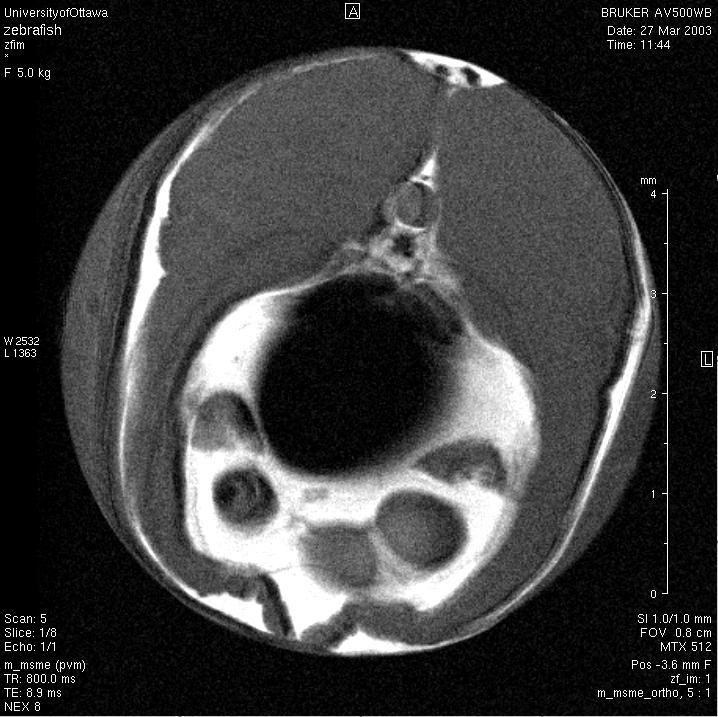

Bruker AVANCE 500